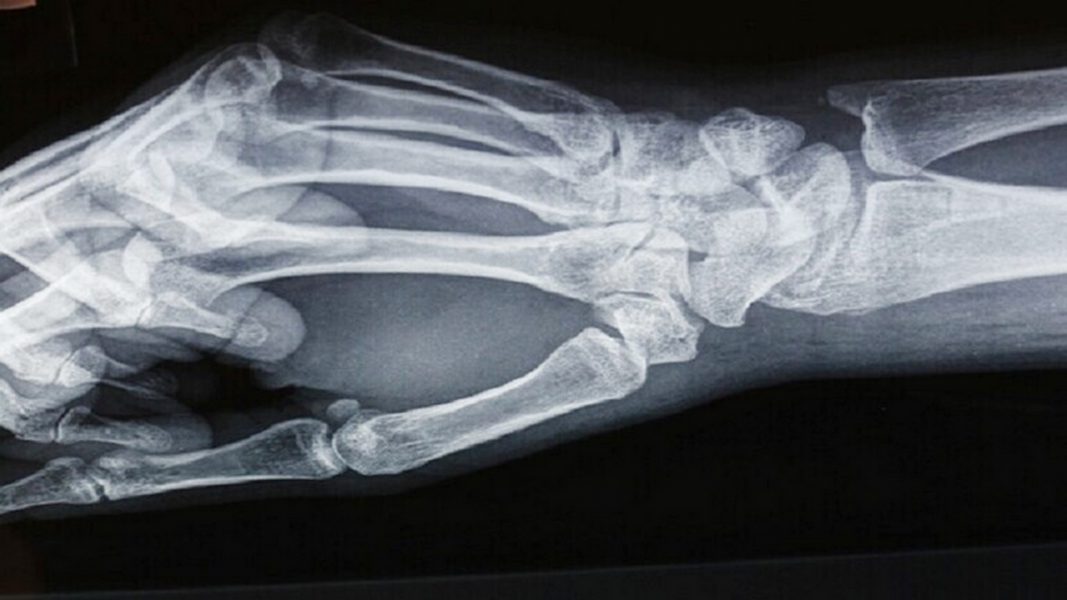

“لانسيت” تنشر نتائج دراسة تربط بين تلوث الهواء وهشاشة العظام

توصلت دراسة جديدة إلى وجود صلة مقلقة بين ارتفاع مستويات تلوث الهواء وهشاشة العظام.

ويزداد خطر الإصابة بهشاشة العظام مع تقدم العمر، وهو شائع بشكل خاص لدى النساء بعد انقطاع الطمث.

وفي دراسة نشرت مؤخرا في مجلة “لانسيت” الطبية، تم جمع بيانات عن مجموعة متنوعة من 9041 امرأة بعد انقطاع الطمث على مدى 6 سنوات.

وباستخدام عناوين المنازل لتقدير كميات أكسيد النيتريك وثاني أكسيد النيتروجين وثاني أكسيد الكبريت وجسيمات PM10، وجد الباحثون أنه مع ارتفاع التلوث، انخفضت كثافة المعادن في العظام في جميع أنحاء الجسم، بما في ذلك الرقبة والعمود الفقري والورك.

ويقول عالم الطب الحيوي، ديدير برادا، من جامعة كولومبيا في نيويورك: “تؤكد النتائج التي توصلنا إليها أن نوعية الهواء الرديئة قد تكون عامل خطر لفقدان العظام، بصرف النظر عن العوامل الاجتماعية والاقتصادية أو الديموغرافية”.

وسلطت الدراسة الضوء على العلاقة بين النيتروجين والعمود الفقري. وارتبطت زيادة بنسبة 10 في المئة من هذا النوع من التلوث على مدى ثلاث سنوات بمتوسط خسارة سنوية بنسبة 1.22 في المئة في كثافة المعادن في عظام العمود الفقري، أي ضعف الكمية التي تسببها الشيخوخة الطبيعية.

وفقا للباحثين، يرجع ذلك إلى موت خلايا العظام الناجم عن آليات بما في ذلك الإجهاد التأكسدي ، حيث تسبب الجزيئات السامة في البيئة أضرارا للجسم.

ورغم أن الدراسة خصصت للنساء بعد انقطاع الطمث، إلا أنها شملت أيضا مجموعة واسعة من المجموعات العرقية والمواقع وأنماط الحياة والخلفيات الاجتماعية والاقتصادية ، مما يزيد من احتمال أن تكون مستويات التلوث السبب الكامن وراء فقدان كثافة العظام لدى نسبة كبيرة من البشر مؤخرا.وكالات